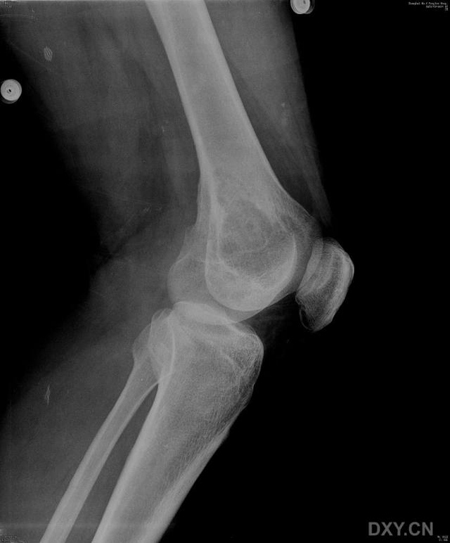

患者,男,38岁,左膝疼痛半月,体检左膝无红肿,无其它既往史

病灶最大径与骨干垂直,病灶呈侵袭性生长,病灶内未见钙化及骨化影,未见骨膜反应,未见软组织肿块,骨壳尚完整.考虑骨巨(良性).

骨巨细胞瘤:病变位于骨端,偏心性分布,其内密度均匀,边缘无硬化,无骨膜反应,无软组织肿块,体检左膝无红肿,无其它既往史,及高发年龄

病灶最大径与骨干垂直,病灶呈侵袭性生长,病灶内未见钙化及骨化影,未见骨膜反应,未见软组织肿块,骨壳尚完整.无硬化边.考虑骨巨(良性).

支持骨巨细胞瘤(病灶偏心性生长,无骨化、钙化及骨膜反应,无软组织肿块,内见纤细间隔)。

ct图片太少,x光片示肿瘤呈横向生长,其内可见纤细分隔,符合骨巨的特点,年龄也符合。